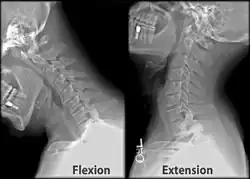

- Neck pain (ex: during movement such extension and flexion)[7]

Once there is an onset of the symptoms in the patient, the patients are screened through cervical-spinal imaging techniques: X-ray, CT, MRI. [1] The scanning technique points out any cervical vertebrae defects and misalignments. (Image 1. and 2.) When cervicocranial syndrome is caused as a result of a genetic disease, then family history and genetic testing aid in making an accurate diagnosis of cervicocranial syndrome.